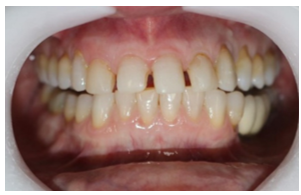

A coleta de dados foi iniciada com a realização de uma consulta inicial, na qual foi conduzida uma anamnese detalhada para levantamento do histórico médico e odontológico do paciente, bem como de suas principais queixas e expectativas em relação ao tratamento estético proposto. Em seguida, foi realizado um exame clínico minucioso com o objetivo de avaliar as facetas previamente instaladas, observando critérios como adaptação marginal, integridade do material restaurador e condições periodontais adjacentes. A saúde bucal geral do paciente também foi analisada nesta etapa, no aspecto inicial foi observado o acúmulo de biofilme causado pela má adaptação cervical, retração gengival, trincas e fraturas derivadas da oclusão desbalanceada, conforme apresenta a figura 1,2,3 e 4.

Figura 1: Vista do lado superior direito.

Figura 2: Vista frontal, região anterior

Figura 3: Vista do lado superior esquerdo.